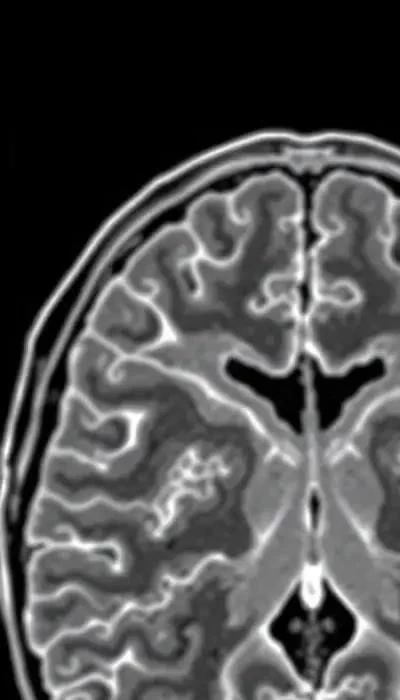

Основной патологической причиной гиперпролактинемии являются опухоли гипофиза, в частности пролактиномы. Пролактиномы – это доброкачественные опухоли, которые вырабатывают избыточное количество пролактина. По статистике, пролактиномы составляют около 30% всех опухолей гипофиза. Другими причинами могут быть прием определенных лекарственных препаратов (например, антидепрессантов, нейролептиков, антигипертензивных средств), заболевания щитовидной железы (гипотиреоз), почечная недостаточность, заболевания печени и травмы грудной клетки.

Лечение агонистами дофамина обычно длительное, иногда пожизненное, особенно при макропролактиномах (опухолях размером более 1 см). Регулярный мониторинг уровня пролактина и МРТ гипофиза необходимы для оценки эффективности лечения и своевременного выявления возможных рецидивов. Важно отметить, что при беременности лечение агонистами дофамина обычно прекращают, так как эти препараты могут оказывать негативное влияние на развитие плода.

Хирургическое вмешательство рассматривается в случаях, когда медикаментозная терапия неэффективна, вызывает непереносимые побочные эффекты или при наличии крупных пролактином, сдавливающих окружающие структуры. Транссфеноидальная хирургия – это наиболее распространенный метод удаления пролактином, который выполняется через нос. Успешность операции зависит от размера опухоли и опыта хирурга.